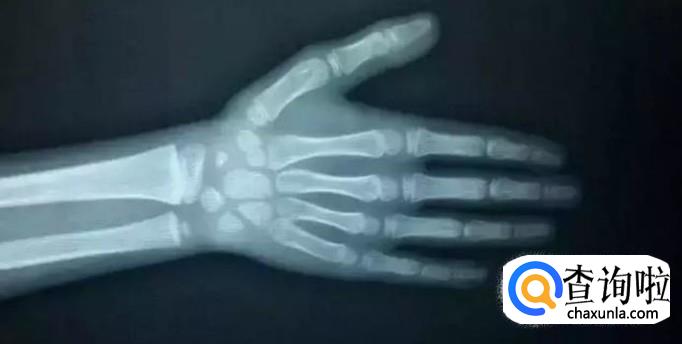

判断孩子能长多高是看孩子的骨龄的,假如发现骨龄增长的速度大于身高增加的速度,则须留意可能是骨骺愈合提前了,这种状况也许会致使孩子不再长个。与自然规律背道而驰的事情一定会有相应的不良影响,所以家长应该时刻关注孩子的生长状况,多与孩子进行一些户外活动,亲近大自然,增进孩子的免疫力,促进骨骼的生长。

所有的诊断结果出来了,女孩得的这个病属于“女性男性化”也叫“女性加两性畸形。并非是患上这种病的孩子以后就是个大高个了。反而,早发育会导致性早熟,使骨骺过早闭合,身体各器官组织会过早停止生长。骨骺过早闭合,会比别人少几年生长发育,造成的后果是将来成年后孩子的身材很矮小。所以,孩子长得太快未必是好事,家长要注意。